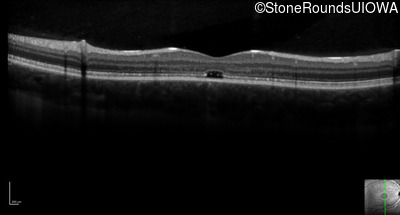

Optical Coherence Tomography - Right - 20/160 +2

Exemplar / OCT Stack

OCT Stack